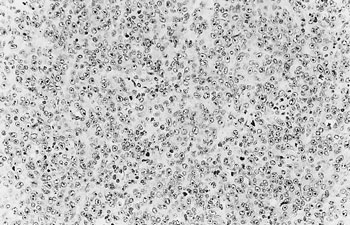

腫瘤の組織像は多様であり,腫瘍細胞がび漫性に増生する部位(図3),腫瘍細胞間にリンパ球様細胞が浸潤する部位,好酸性細胞と好塩基性細胞が結節性に増生する部位,線維に富む間質で区画され,好酸性細胞が腺様構造をつくる部位を認めた.腫瘍細胞は細胞質に乏しく,核は類円形でクロマチンに乏しく,明瞭な核小体を1〜数個有し,分裂像が散見された.腫瘍細胞はPAS・オレンジG染色陰性,抗下垂体産生ホルモン抗体を1次抗体とした免疫染色で陰性であった. |

| 図3 |

嫌色素性の腫瘍細胞のび慢性増殖部(HE染色 ×200倍).(富山県食検出題) |